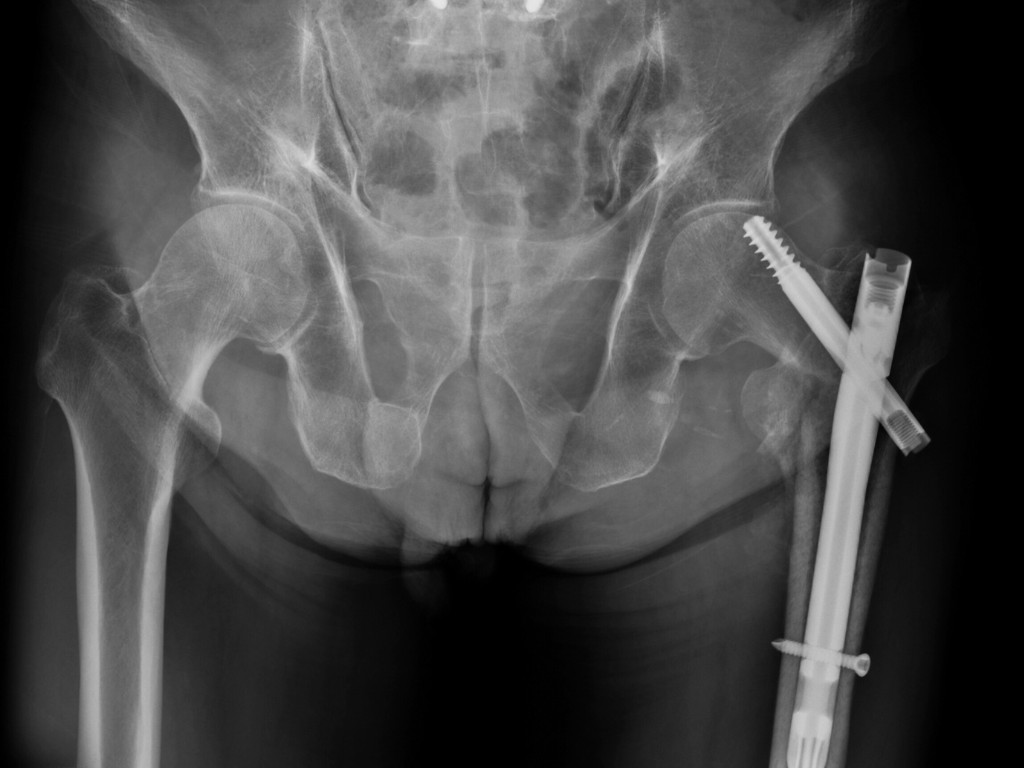

Clear, advanced diagnosis: Using advanced imaging like MRI and X-ray, Dr. Mehta identifies the underlying damage, so your treatment is precise.

Step 3: Investigations

To get a detailed view of your hip health and find the underlying issue, Dr. Mehta may recommend imaging tests like X-rays or an MRI.